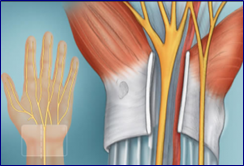

1) τη μορφολογία των περιφερικών νεύρων με αποκάλυψη εστιακών αλλοιώσεων (όπως στενώσεις, οιδήματα ή υπερτροφίες)

2) την αιτία πίεσης ενός νεύρου (π.χ. αιμάτωμα, γάγγλιο κ.α.)

1) Σε συμτπώματα πίεσης ενός νεύρου (πιεστική νευροπάθεια), με στόχο την αποκάλυψη της αιτίας αυτής (π.χ. εύρεση της αιτίας του συνδρόμου καρπιαίου σωλήνα).